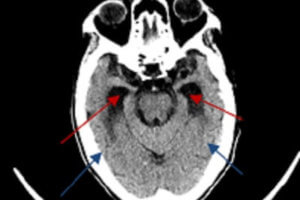

Cavernous Sinus Anatomy

Situated in the midline just above the skull base and bridging the sphenoid and temporal bones, the cavernous sinus is a collection of venous channels that serves as a major conduit for... Read more »